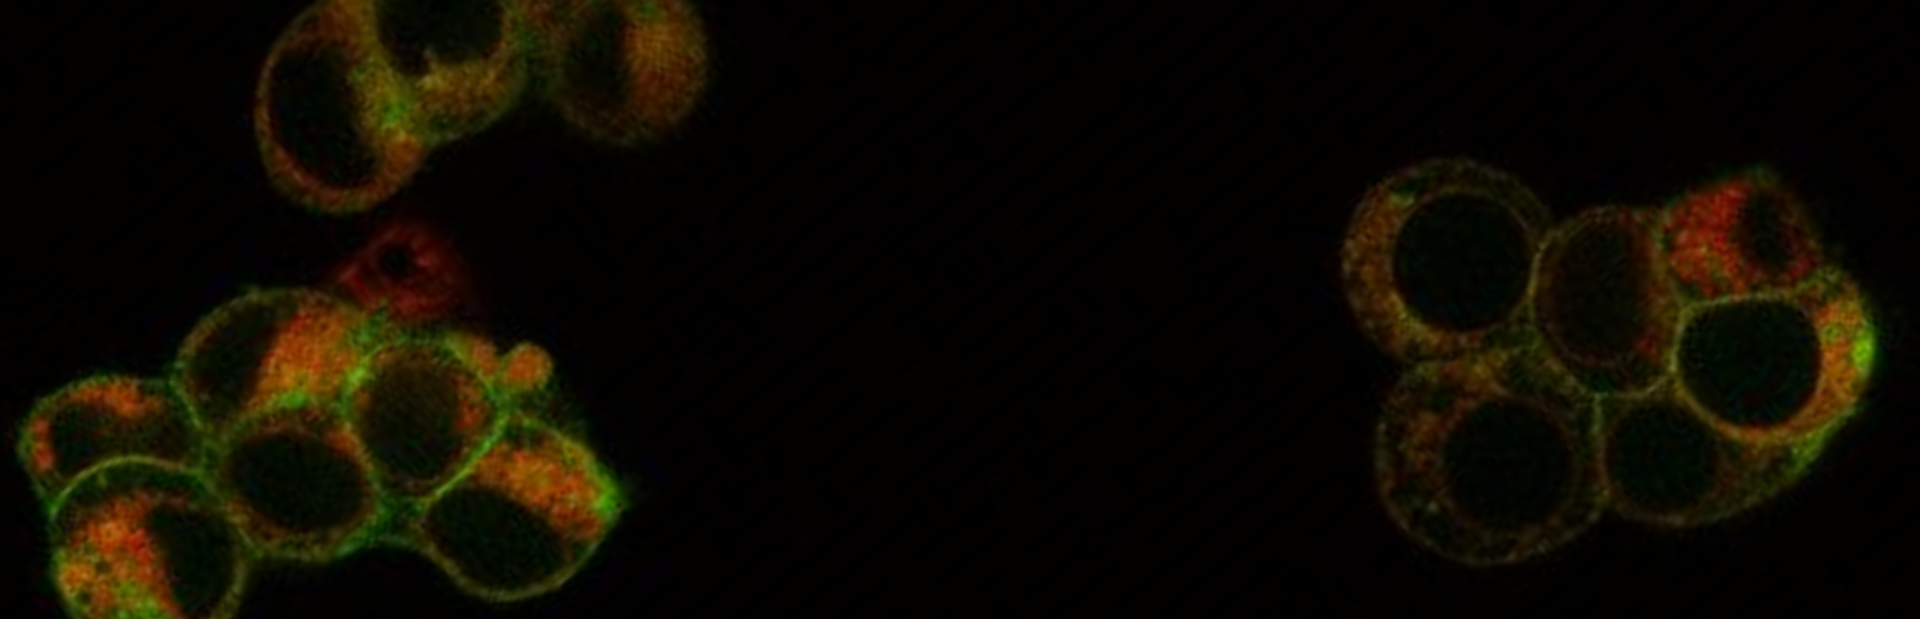

Discovering the mechanisms of clinically relevant cell death

Understanding the molecular mechanisms of cell death has been at the center of medical research for decades. In the past, apoptosis was at the center of this effort. However, emerging evidence has demonstrated that necrosis—a process once considered passive and unregulated—is, in fact, a well-regulated mechanism. Regulated necrosis is characterized by the rupture of the plasma membrane and the release of intracellular content, so-called damage associated molecular patterns (DAMPs). This process is now recognized as a critical step in the pathophysiology of various diseases, including acute kidney injury and the progression to chronic kidney disease (CKD).

Our lab investigates the distinct forms of regulated necrosis, including necroptosis and ferroptosis, and their roles in renal injury, nephron loss, and organ transplantation. Understanding these pathways not only clarifies disease mechanisms but might also reveal novel options for therapeutic intervention aimed at preventing or mitigating kidney damage.